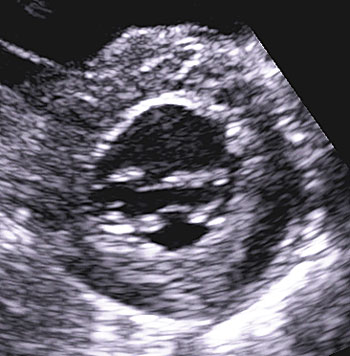

Bilddiagnostik med bland annat ultraljud och doppler

Ultraljudsundersökning av hjärtat påvisar ­hypertrofi – oftast i kammarseptum, men alla delar av hjärtat kan påverkas (Figur 3, 4 och 5). Det förekommer en variant med enbart apikal hypertrofi. Med dopplerundersökning kan förhöjda hastigheter över vänsterkammarens utflödesregion påvisas i vila hos ungefär en tredjedel, medan hos ytterligare cirka en tredjedel förhöjd gradient (tryckskillnad) kan provoceras fram genom fysiologisk belastning, Valsalvas manöver eller läkemedel. Den metod som numera rekommenderas är fysiologisk belastning på cykelergometer eller gångmatta, vilket är av värde om ingen gradient ses vid vila då anamnesen indikerar en dynamisk gradient.

Figur 4. Ekokardiografi, parasternal kortaxel, vid koncentrisk hypertrofi.